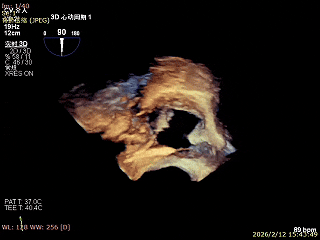

三尖瓣术前评估

三尖瓣反流(重度);肺动脉高压(中度);二尖瓣反流(中度);双房左室增大;左室顺应性减低。

术前食道超声评估

三尖瓣关闭不全重度(4+,平均缩流颈10mm),反流口以前隔、中央为主,部分后隔,瓣叶未见明显脱垂及GAP,三尖瓣环扩张(瓣环平均径43mm),二尖瓣中-重度反流,肺动脉高压(PASP:44mmHg)。